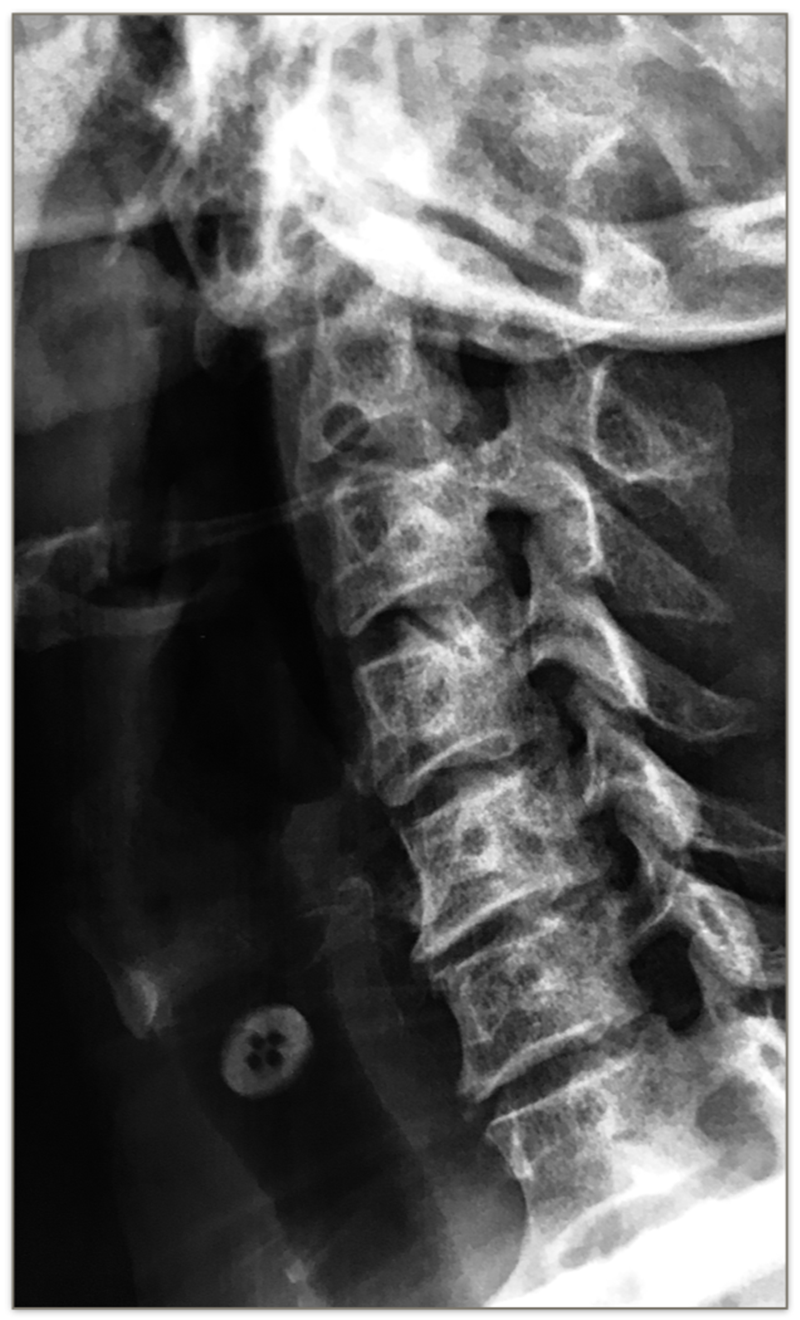

术前X线

MRI:C3-4后方可见脊髓高信号改变

颈椎斜位X光片有助于观察钩椎关节